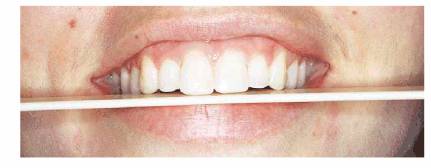

Figure 17-11D and E: This young woman's defective amalgam restorations were replaced in 1968 with tooth- colored restorations. At that time, and during the ensuing few years of maintenance recalls, she was advised to have a bite appliance constructed for her severe bruxism habit.

Figure 17-11F to H: She returned 31 years after her first appointment with an extremely worn dentition.

Figure 17-11I and J: Treatment consisted of crown lengthening and full crowns, which restored the patient's smile and her self-confidence.